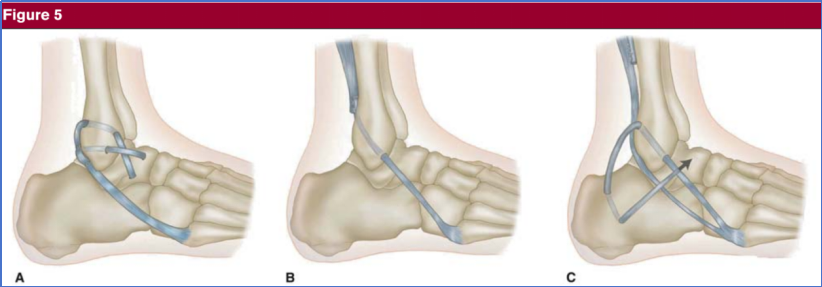

图11 采用自体移植物联合挤压螺钉,对慢性踝关节外侧不稳患者进行距腓前韧带(ATFL)与跟腓韧带(CFL)解剖性重建,具体如下:(A)踝关节抗内翻术(Anti-ROLL)示意图; (B)Y 型移植物;(C)使用挤压螺钉将 Y 型移植物固定于腓骨、距骨及跟骨的骨隧道内。